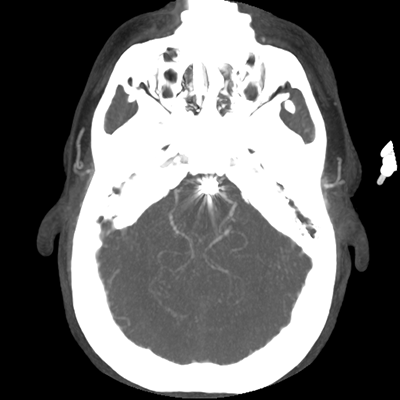

The patient goes down to CT. The following images are obtained. The subdural fluid collection is stable, as is the ventricular caliber.

Starting with the non-contrast head CT, we can appreciate that there's actually not much residual subarachnoid blood at all; it's essentially all resorbed already (and cleared through the EVD). The ventricular caliber is stable. With the CTA head (for convenience's sake, the MIPs were shown), it's subtle, but we can see that the PCAs on each side are not as smooth and regular. The right MCA, starting at the bifurcation, also becomes narrower. This is [radiographic] vasospasm. Now, looking at the CT perfusion-- specifically, the Tmax (MTT) map that were selected-- there's clearly some abnormality within the bilateral cerebellar hemispheres and occipital lobes. Not a lot, but it's there. Delving further into this map, we can appreciate that the areas of abnormality are mainly green, signifying that these areas have Tmax > 6 seconds. This is the threshold that is specific, not sensitive, for vasospasm.

Putting this all together, we have thus identified radiographic vasospasm with the vessel imaging, with perfusion abnormalities that are concordant with it. Does the area of vasospasm and hypoperfusion correlate with the patient's clinical exam?

Yes! It does. The patient had a decline in level of consciousness with diffuse loss of motor function. This does correlate to the basilar territory. (Alternatively, bilateral MCA vasospasm could also be responsible, reminding us that a decline in consciousness could technically be focal/multifocal.) Thus, we can say that this patient does have clinical vasospasm. Whether this will develop into irreversible DCI remains to be seen; at least, the non-contrast head CT and the other portions of the CT perfusion (not shown) currently don't [yet] suggest infarction.